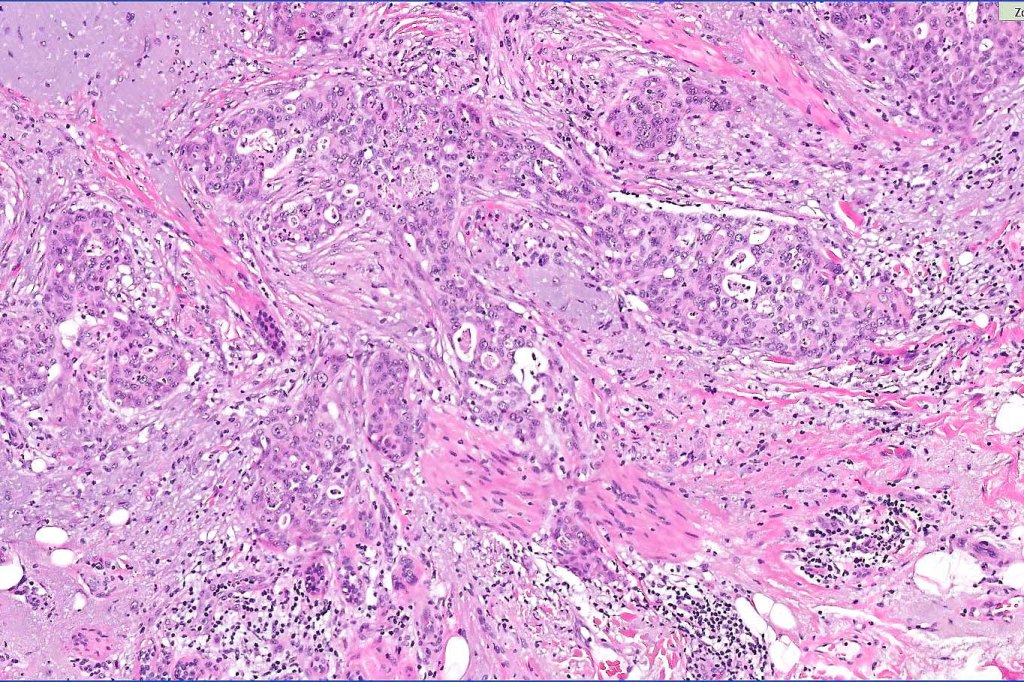

•Widely infiltrating biphasic tumor

•Adenocarcinoma in deeper reaches

•Deep part may show both ducts and glands

•Often extends to the subcutaneous fat

•Perineural infiltration is commonly seen